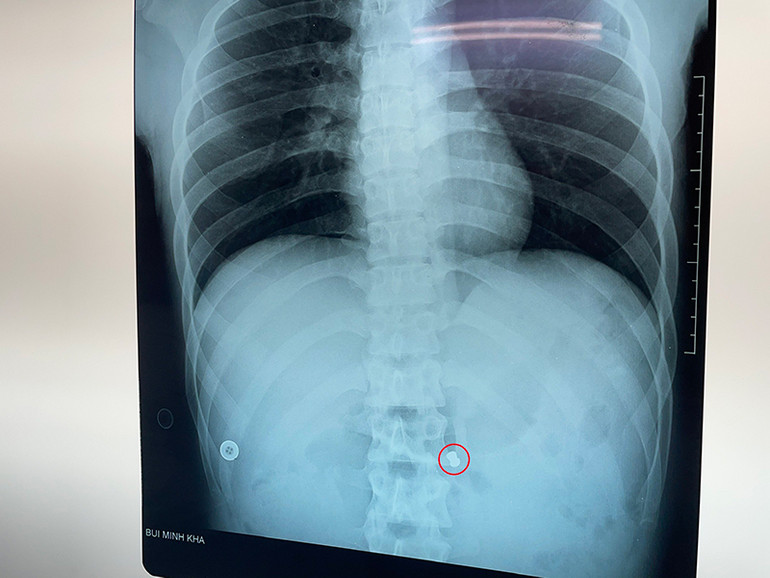

Hình ảnh chụp CT bụng bệnh nhân với vết thương xuyên thấu gây thủng động mạch chủ bụng.

Thám sát thấy viên đạn chì, nghi của súng hơi, kích thước 2,5x0,8 cm nằm cạnh động mạch mạc treo tràng trên và lấy được đầu viên đạn.